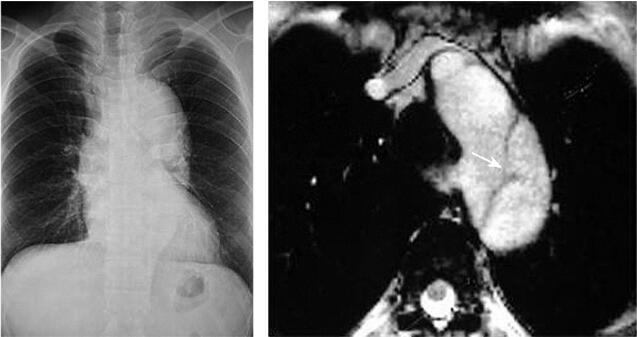

X线片表现:主动脉弓降部明显扩张,左心缘饱满,肺血无明显改变。

MRI:MR true FISP序列,清楚显示真假腔、内膜破口,并在电影中观察到血流在真假腔中运动。MRA表现为降主动脉呈“双腔”主动脉,真腔受压变窄,假腔较大,假腔自降主动脉延续至腹主动脉;头臂血管分支均起自真腔,腹腔干及肠系膜上动脉均起自真腔。

图1 主动脉夹层